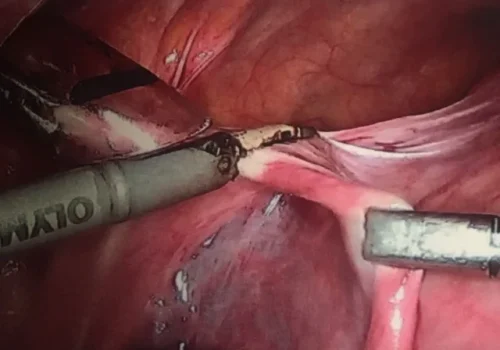

Procedure

She subsequently underwent Total Laparoscopic Hysterectomy.